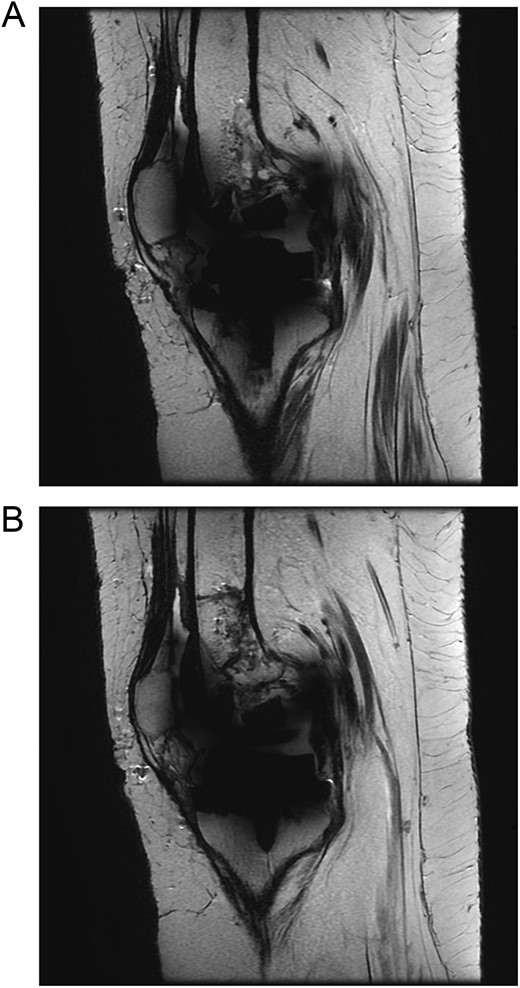

Upon examination in the emergency room, the patient was vitally stable, alert, and oriented. Her skin was intact, showing a healed wound. Mild swelling was noted over the left knee joint, with no erythema or ecchymosis. She had tenderness over the medial surface of the knee. The active ROM was from 0º to 90º and was limited due to pain; the passive ROM was from 0º to 110º with a clicking sound during flexion. Soft compartments were noted, and distal neurovascular examination was unremarkable (Fig. 2).

(A) Anteroposterior view of the left knee in the emergency department. (B) Lateral view of the left knee in the emergency department.